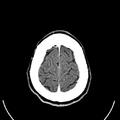

التصوير المَقْطَعي الحاسوبيX-ray computed tomography نظام تصوير بالأشعة السينية، يُسْتخدم لتصوير مختلف أجزاء الجسم مثل الرأس والقلب والبطن. ويستعين الأطباء بالتصوير المقطعي الحاسوبي على تشخيص الأمراض وعلاجها. وتسمى هذه التقنية أيضًا التصوير المقطعي المحوسب أو التصوير المقطعي المحوري المحوسب.

ويستعمل الأطباء فحوص التصوير المقطعي الحاسوبي لتشخيص كثير من الحالات مثل الأورام والإصابات وتجلطات الدم وكسور العظام. ويساعد التصوير المقطعي الحاسوبي أيضًا في معالجة بعض الأمراض، التي قد تتطلب جراحة بطريقة أخرى. فمثلا،ً يمكن للأطباء استعمال التصوير المقطعي الحاسوبي لإرشادهم إلى إدخال القثطار (أنبوب رفيع) إلى خُرّآج في الجسم لسحب الصديد من المنطقة الملوثّة.

يمكن للأطباء أن ينظروا داخل جسم المريض عن طريق طلب إجراء مسح للعظام والأوعية الدموية والأدمغة والأنسجة الرخوة بفضل ماسح التصوير المقطعي الحاسوبي (CT). بعد إجراء أول فحص طبي بالأشعة المقطعية للمريض في عام 1971، استخدم أطباء الأشعة عمليات المسح لتشخيص الأورام والصدمات والتخطيط للعلاج الطبي والجراحي والإشعاعي في جميع أجزاء جسم الإنسان تقريباً.